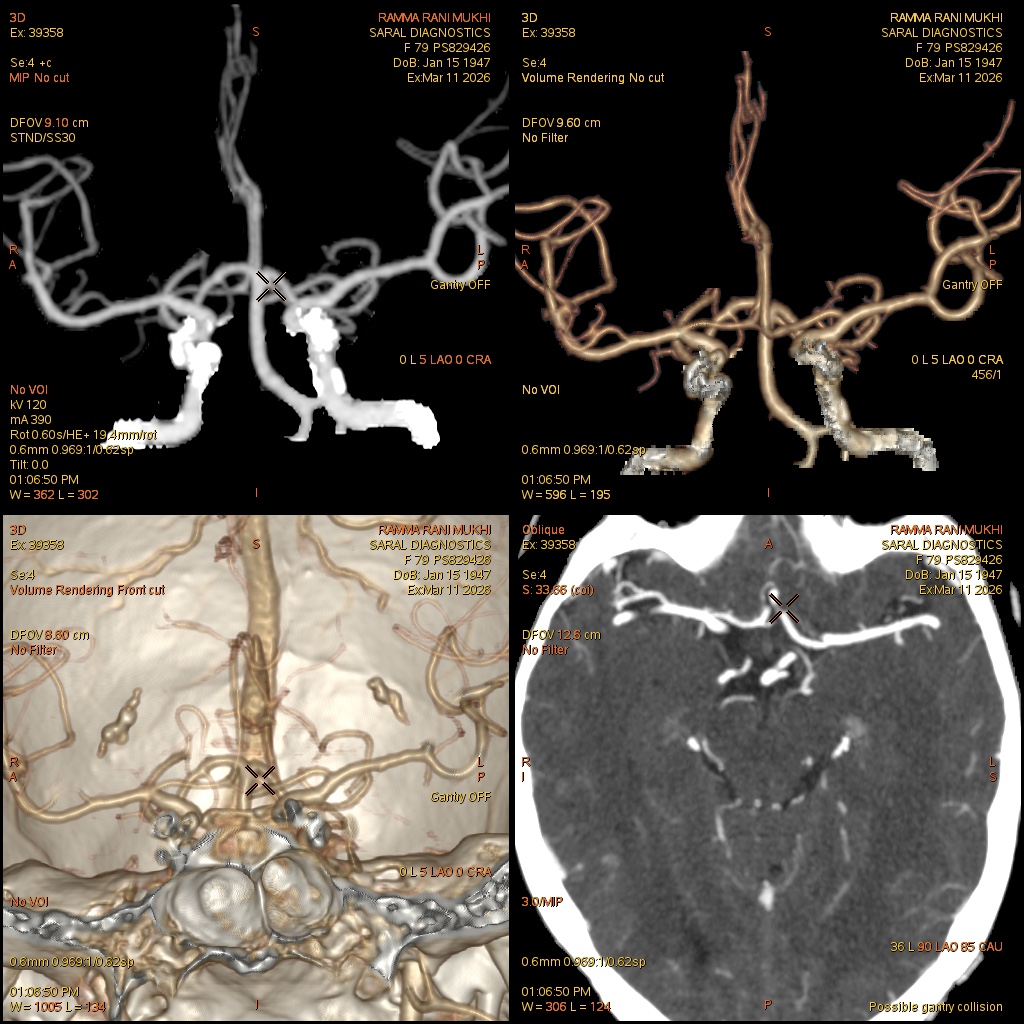

Reference Image

Angiography Brain (Scan charges only)

This is a CT angiography of the blood vessels of the brain, done without contrast charges included. It captures detailed images of arteries supplying the brain, including the Circle of Willis. Doctors use this scan to detect early signs of stroke, vessel narrowing, aneurysms, congenital abnormalities, or bleeding risks. It is useful for patients with severe headaches, dizziness, neurological symptoms, or trauma. The scan is quick and non-invasive, providing essential information for initial evaluation. Contrast may be added later if required.